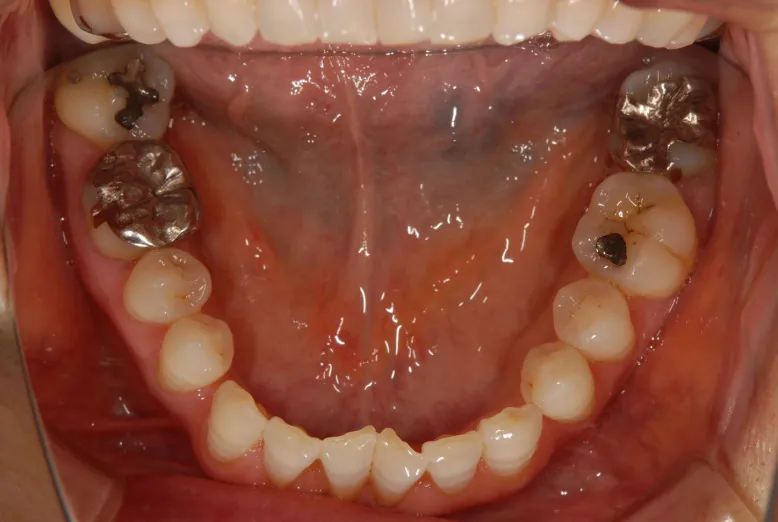

CASE1 60代女性 ダイレクトボンディングによる修復治療

初診

歯石除去で来院されました。

除去後、話を聞くと上顎の前歯の歯と歯の間が離れていることが

以前より気になっていると仰られ、治療計画を立案。

レントゲン写真を撮影。

口腔内写真の撮影

残っている歯の問題点などを解析

さまざまな方向性から、歯のバランスや問題点を解析。

治療計画の立案を行います。